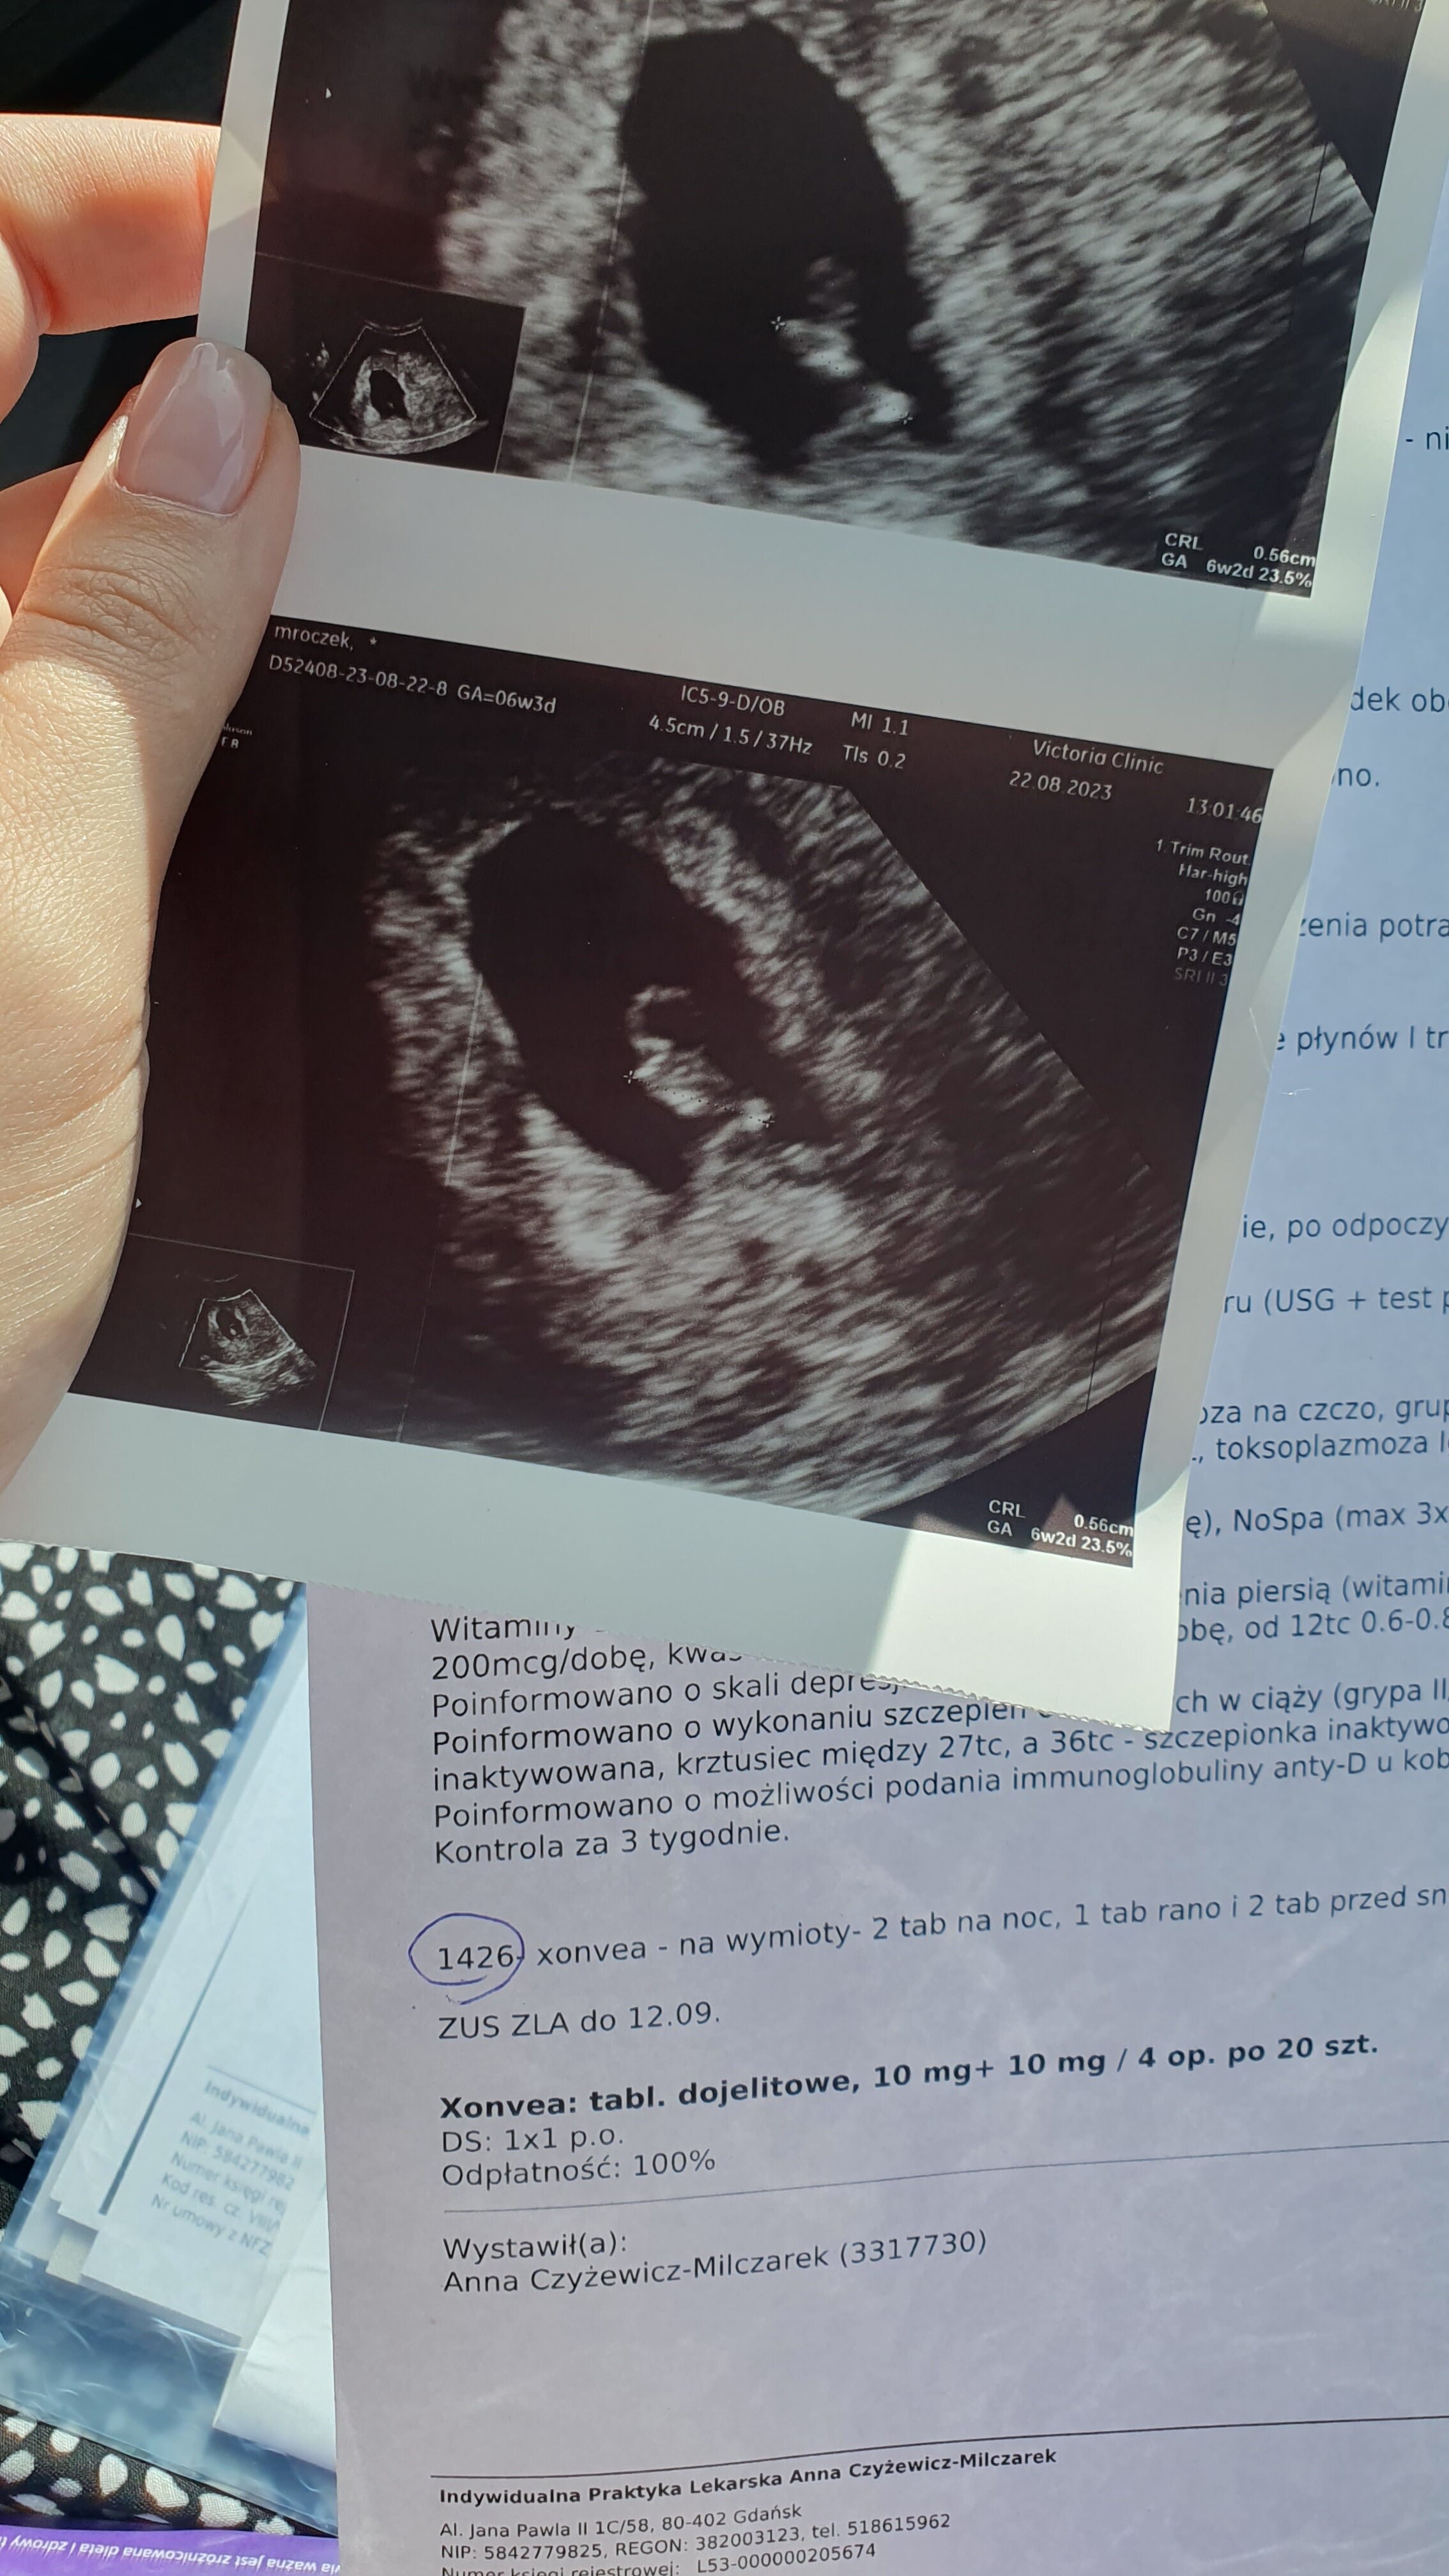

Melduję się po mojej dzisiejszej wizycie, z OM dziś 6+3, wg usg 6+2 ale ciężko było zmierzyć bo malec się chował, piąstki pod pupą zawsze pomagają

najważniejsze, że wszystko jest dobrze, malec rośnie a serduszko bije, wrzucam fotkę mojego groszka